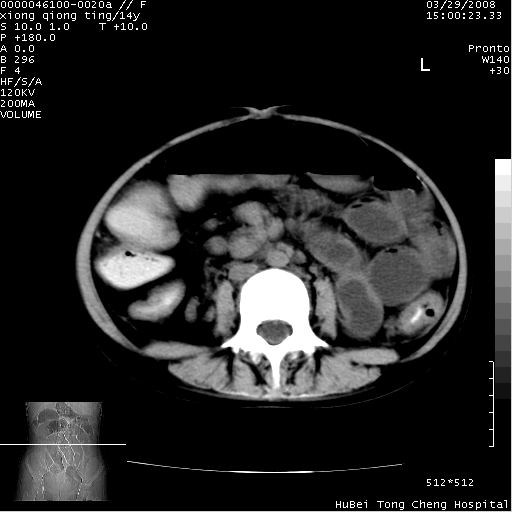

患儿 女,14岁。不规则发热一周,偶感头痛,无抽搐及呕吐。pe:神清,精神差,双侧瞳孔等大等圆,对光反射敏感,双肺未闻及明显啰音,心音有力,腹部触之似揉面感,下腹压痛,无反跳痛。

腹部b超提示:子宫缩小,盆腔积液,肝实质回声密集。

临床诊断:发热原因待查:1)腹部结核感染。2)伤寒?3)结缔组织病?

中下腹及盆腔ct轴位平扫+增强扫描(层厚10mm,螺距1.0,重建间隔10mm),图像如下:

(注:患儿检查当日上午9时口服胃肠道对比剂,下午3时许行ct扫描检查,未行对比剂直肠保留灌肠,检查当日患儿腹泻)

中下腹及盆腔ct轴位扫描(ps+ce)提示:腹部肠管明显充气扩张,并见数个不同宽度之气液平面;疑不全性肠梗阻或肠郁张。临床会诊考虑为患儿腹泻,肠郁张所致;后来未经特殊处理,患儿大便恢复正常,亦无腹胀。

临床出院诊断:1)结核性腹膜炎。2)腹膜后淋巴结结核。3)脂肪肝。